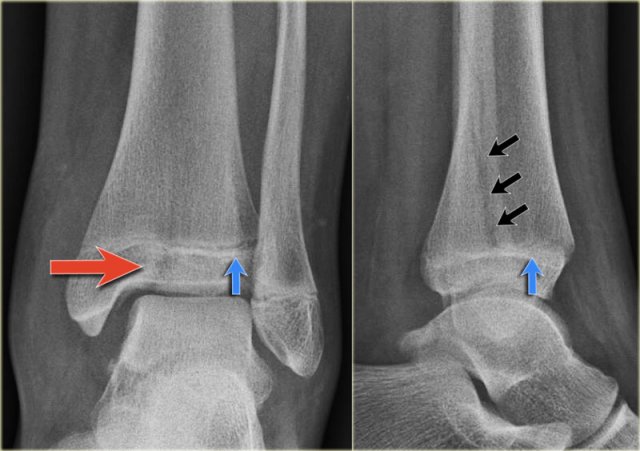

Study the images and then scroll to the next images.

The fracture through the epiphysis can be easily missed (blue arrow).

The fracture through the growth plate is only seen on CT.

Continue with the CT images.

The CT-images nicely display the fracture through the growth plate and the epiphysis.